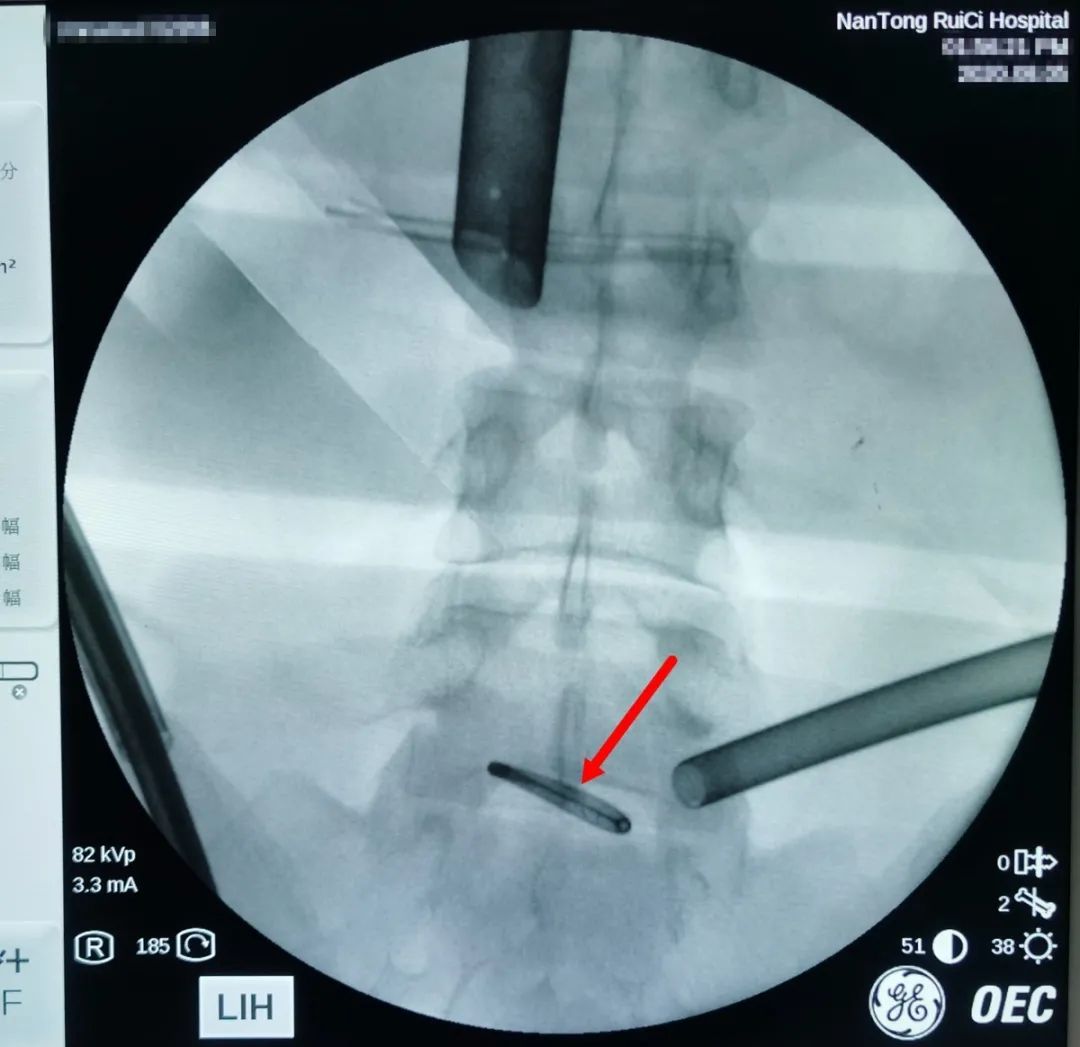

△通過術(shù)中X光,對(duì)節(jié)育環(huán)進(jìn)行標(biāo)記定位。

通過反復(fù)的X光定位,醫(yī)生終于發(fā)現(xiàn)了節(jié)育環(huán)的蹤跡,這枚“O”型節(jié)育環(huán)已經(jīng)跑到了乙狀結(jié)腸中段右側(cè)系膜內(nèi),并且穿透了乙狀結(jié)腸右側(cè)壁肌層,貫穿腸腔。醫(yī)生分離切開腸系膜后,看見有近一半的節(jié)育環(huán)嵌頓在腸腔內(nèi)。